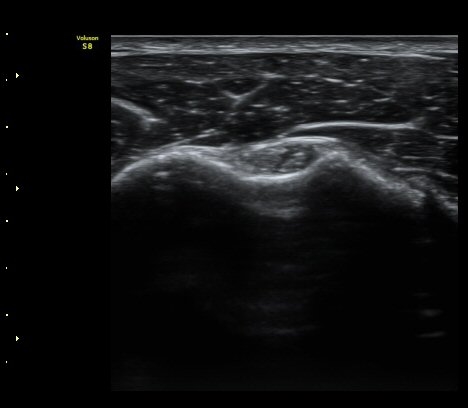

°ß°©ÇÏ±Ù°Ç Á¾´Ü¸é°Ë»ç¿¡¼­ ƯÀÌ ¼Ò°ßÀ» º¸ÀÌÁö ¾ÊÀ½(»çÁø 2, 3)